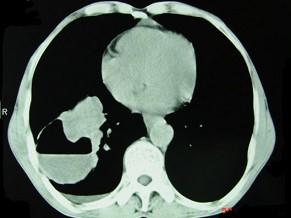

问题 男,76岁,胸痛伴咳嗽,咯血低热一月,CT检查如图,最可能的诊断为 ( )

选项 A、右下肺包虫病 B、右侧包裹性积液 C、右下肺癌伴空洞形成 D、右下肺囊肿 E、右下肺脓肿

答案 C